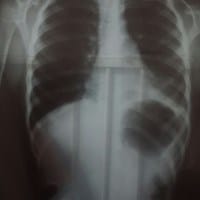

Problemas con sistema respiratorio de mi hija, le han diagnosticado neumonia.

Hace un par de semanas que mi hija tiene problemas respiratorios, ha estado sometida a fiebre, y hemos ido con distintos especialistas que nos han recomendado que le hagamos nebulizaciones cada cuatro horas, últimamente la situación empeoró y en la...